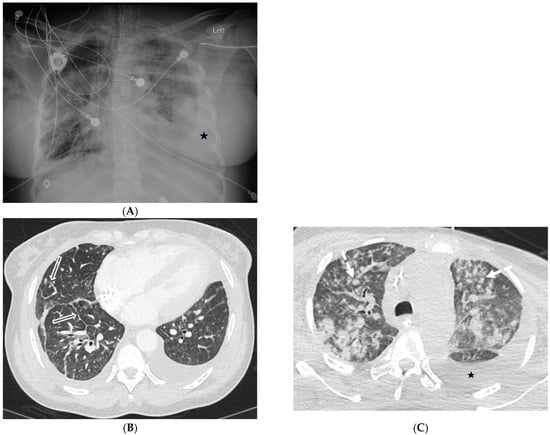

2.1. COVID-19 Pneumonia

2.2. Bacterial Pneumonia

2.4. Pneumocystis Jiroveci Pneumonia (PJP)